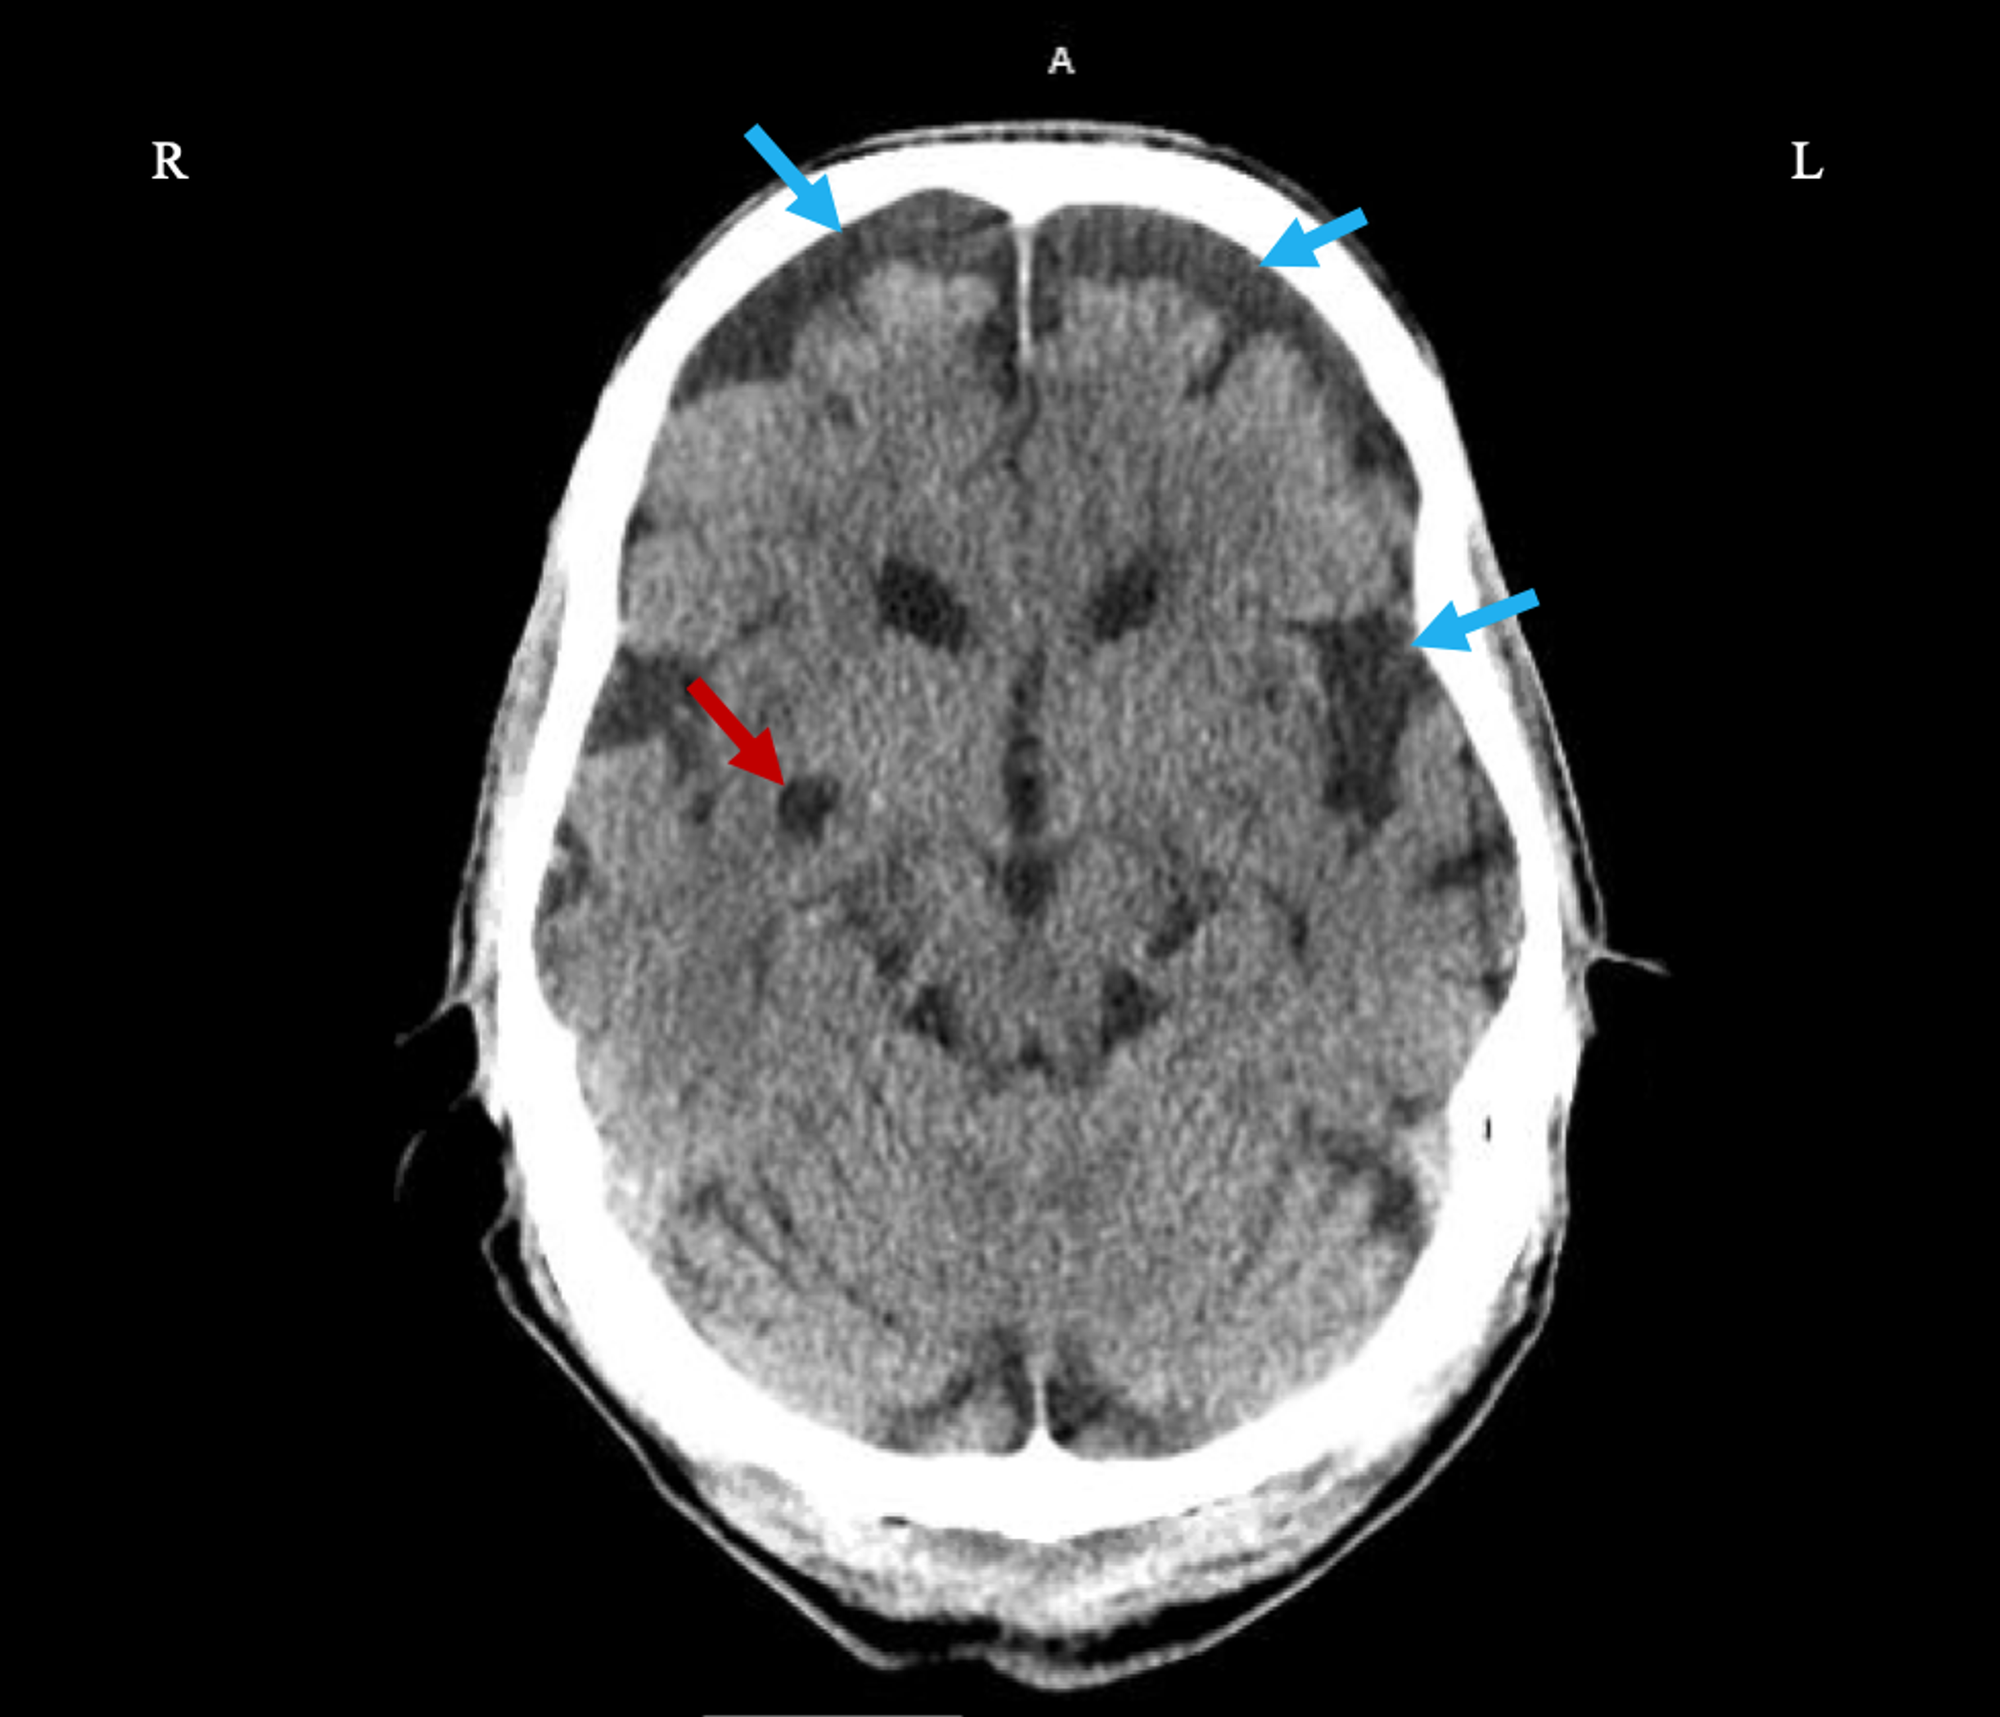

CreutzfeldtJakob disease, CT scan Stock Image C055/6182 Science Creutzfeldt-Jakob Disease Myoclonus The acute or subacute onset of myoclonus. This condition belongs to a group of. It occurs worldwide and has several forms and. Most patients die within 12 months following disease manifestation. — myoclonus occurs as one, or the only, seizure manifestation while it can also present as a peculiar type of. Creutzfeldt-Jakob Disease Myoclonus.

CreutzfeldtJakob disease (CJD). A 69yearold male with a 5month Creutzfeldt-Jakob Disease Myoclonus The acute or subacute onset of myoclonus. It occurs worldwide and has several forms and. Most patients die within 12 months following disease manifestation. This condition belongs to a group of. — myoclonus occurs as one, or the only, seizure manifestation while it can also present as a peculiar type of. Creutzfeldt-Jakob Disease Myoclonus.

CreutzfeldtJakob disease, CT scan Stock Image C058/4675 Science Creutzfeldt-Jakob Disease Myoclonus This condition belongs to a group of. It occurs worldwide and has several forms and. — myoclonus occurs as one, or the only, seizure manifestation while it can also present as a peculiar type of. The acute or subacute onset of myoclonus. Most patients die within 12 months following disease manifestation. Creutzfeldt-Jakob Disease Myoclonus.